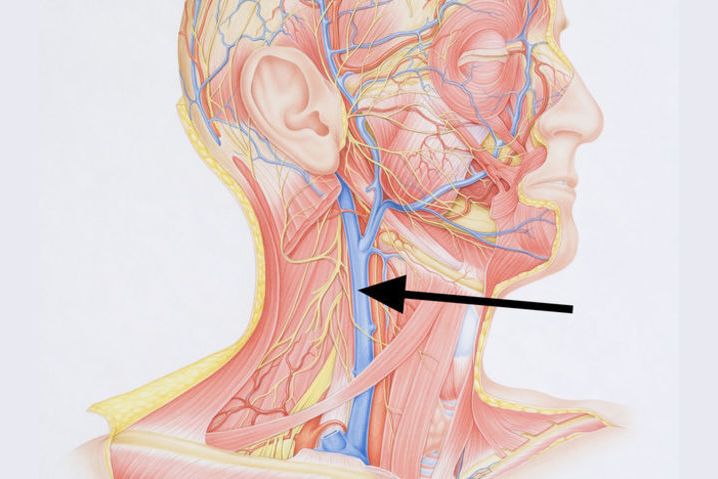

Анатомия внутренней яремной вены: КТ изображения